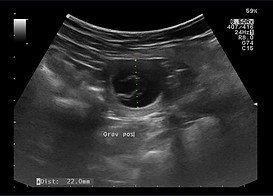

27. Tag: Ultraschall - Ende der Embryonalperiode

Um den 28. Tag ist die Plazentabildung beendet. Sterben die Fruchtanlagen bis zu diesem Tag ab, werden sie meist unauffällig resorbiert. Am Ende dieser Embryonalperiode sind beim Hund alle wichtigen Organsysteme im Groben angelegt, die endgültige Körperform ist bereits in ihren Grundzügen erkennbar und die Gesichter nehmen Gestalt an. Die Nervenstränge im Rückenmark werden gebildet. Ab diesem Zeitpunkt heißt es auch nicht mehr Embryo, sondern Fötus.

Der Herzschlag der Embryos/der Föten ist von geübten Personen wahrnehmbar. Besonders zwischen dem 24. und 28.Tag der Trächtigkeit sind die 1 bis 2 cm großen Ampullen als kugelige Wölbungen durch erfahrene Geburtshelfer zu ertasten